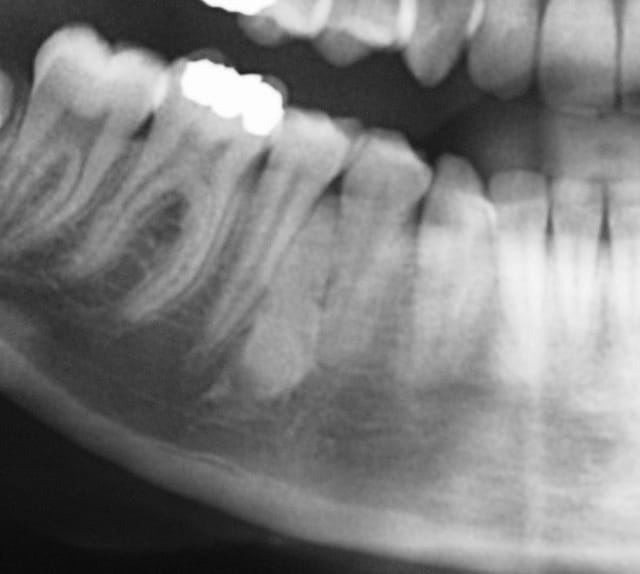

Cookie Consent byPrivacyPolicies.comimage radio opaque - Eugenol

image radio opaque

auriez-vous une idée de ce que c'est et quelle conduite à tenir?

pas de signe clinique, découvert a la radio.

Pour ma part, je pensais à un cémentome...cat?